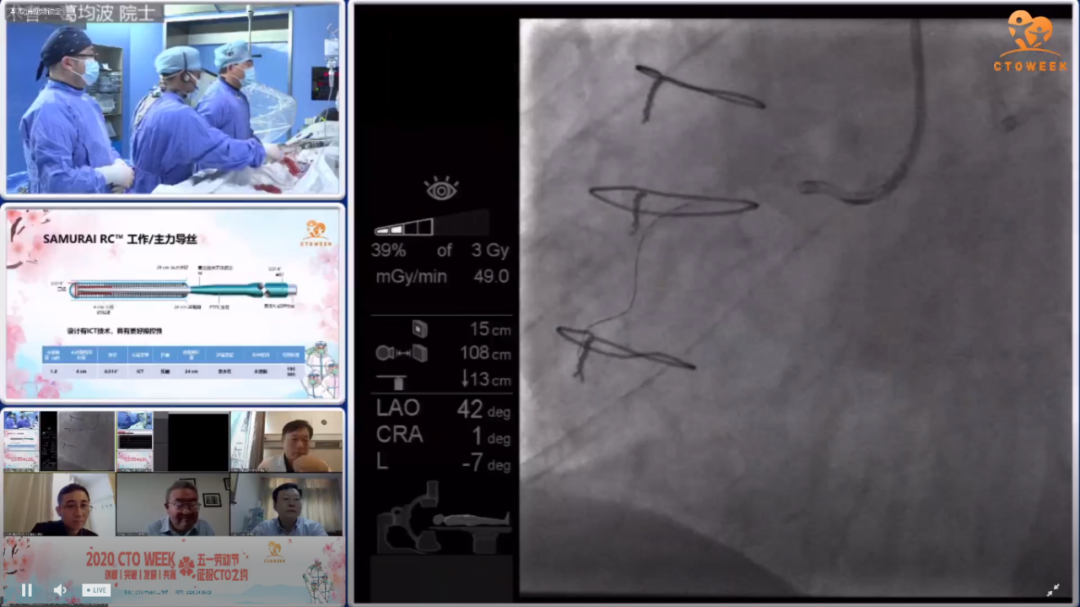

复旦大学附属中山医院葛均波院士、钱菊英院长、葛雷教授、黄东教授、戴宇翔教授、马剑英教授和陆浩教授为我们带来了7台精彩的CTO手术。J-CTO评分2-4分,其中LAD-CTO 2例,RAC-CTO 5例。手术展示了reverse-CART技术,ADR技术。